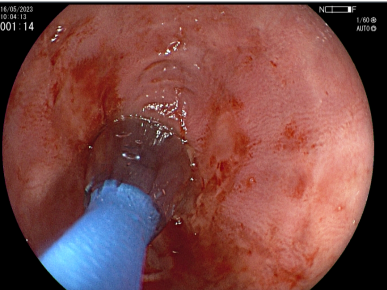

Coledocoscopía

Estudio Detallado de la Vía Biliar

Requiere de Equipamiento Especial

Permite Toma de Muestras Bajo Visión Directa de los Conductos Biliares